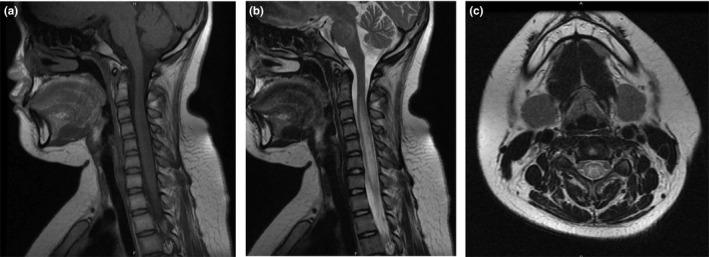

Magnetic resonance imaging of the brain revealed multiple hyperintense lesions at the subcortical level on fluid-attenuated inversion recovery (FLAIR), and MRI of the spinal cord revealed longitudinally segmented hyperintense lesions at the spinal cord on T2-weighted images. The patient was treated with methylprednisolone and gancyclovir, and had a favorable recovery. Subsequent MRI of the brain and cervical cord showed the previous abnormal hyperintensities had markedly disappeared.

A rare case of ADEM with longitudinal segmented hyperintense lesions at the spinal cord on T2-weighted images was presented. Excellent response to ADEM treatment with high-dose steroids was reported resulting in a remarkable neurological recovery. A long-term follow-up is needed for prognosis.